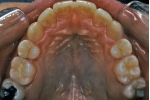

治療後2年経過時